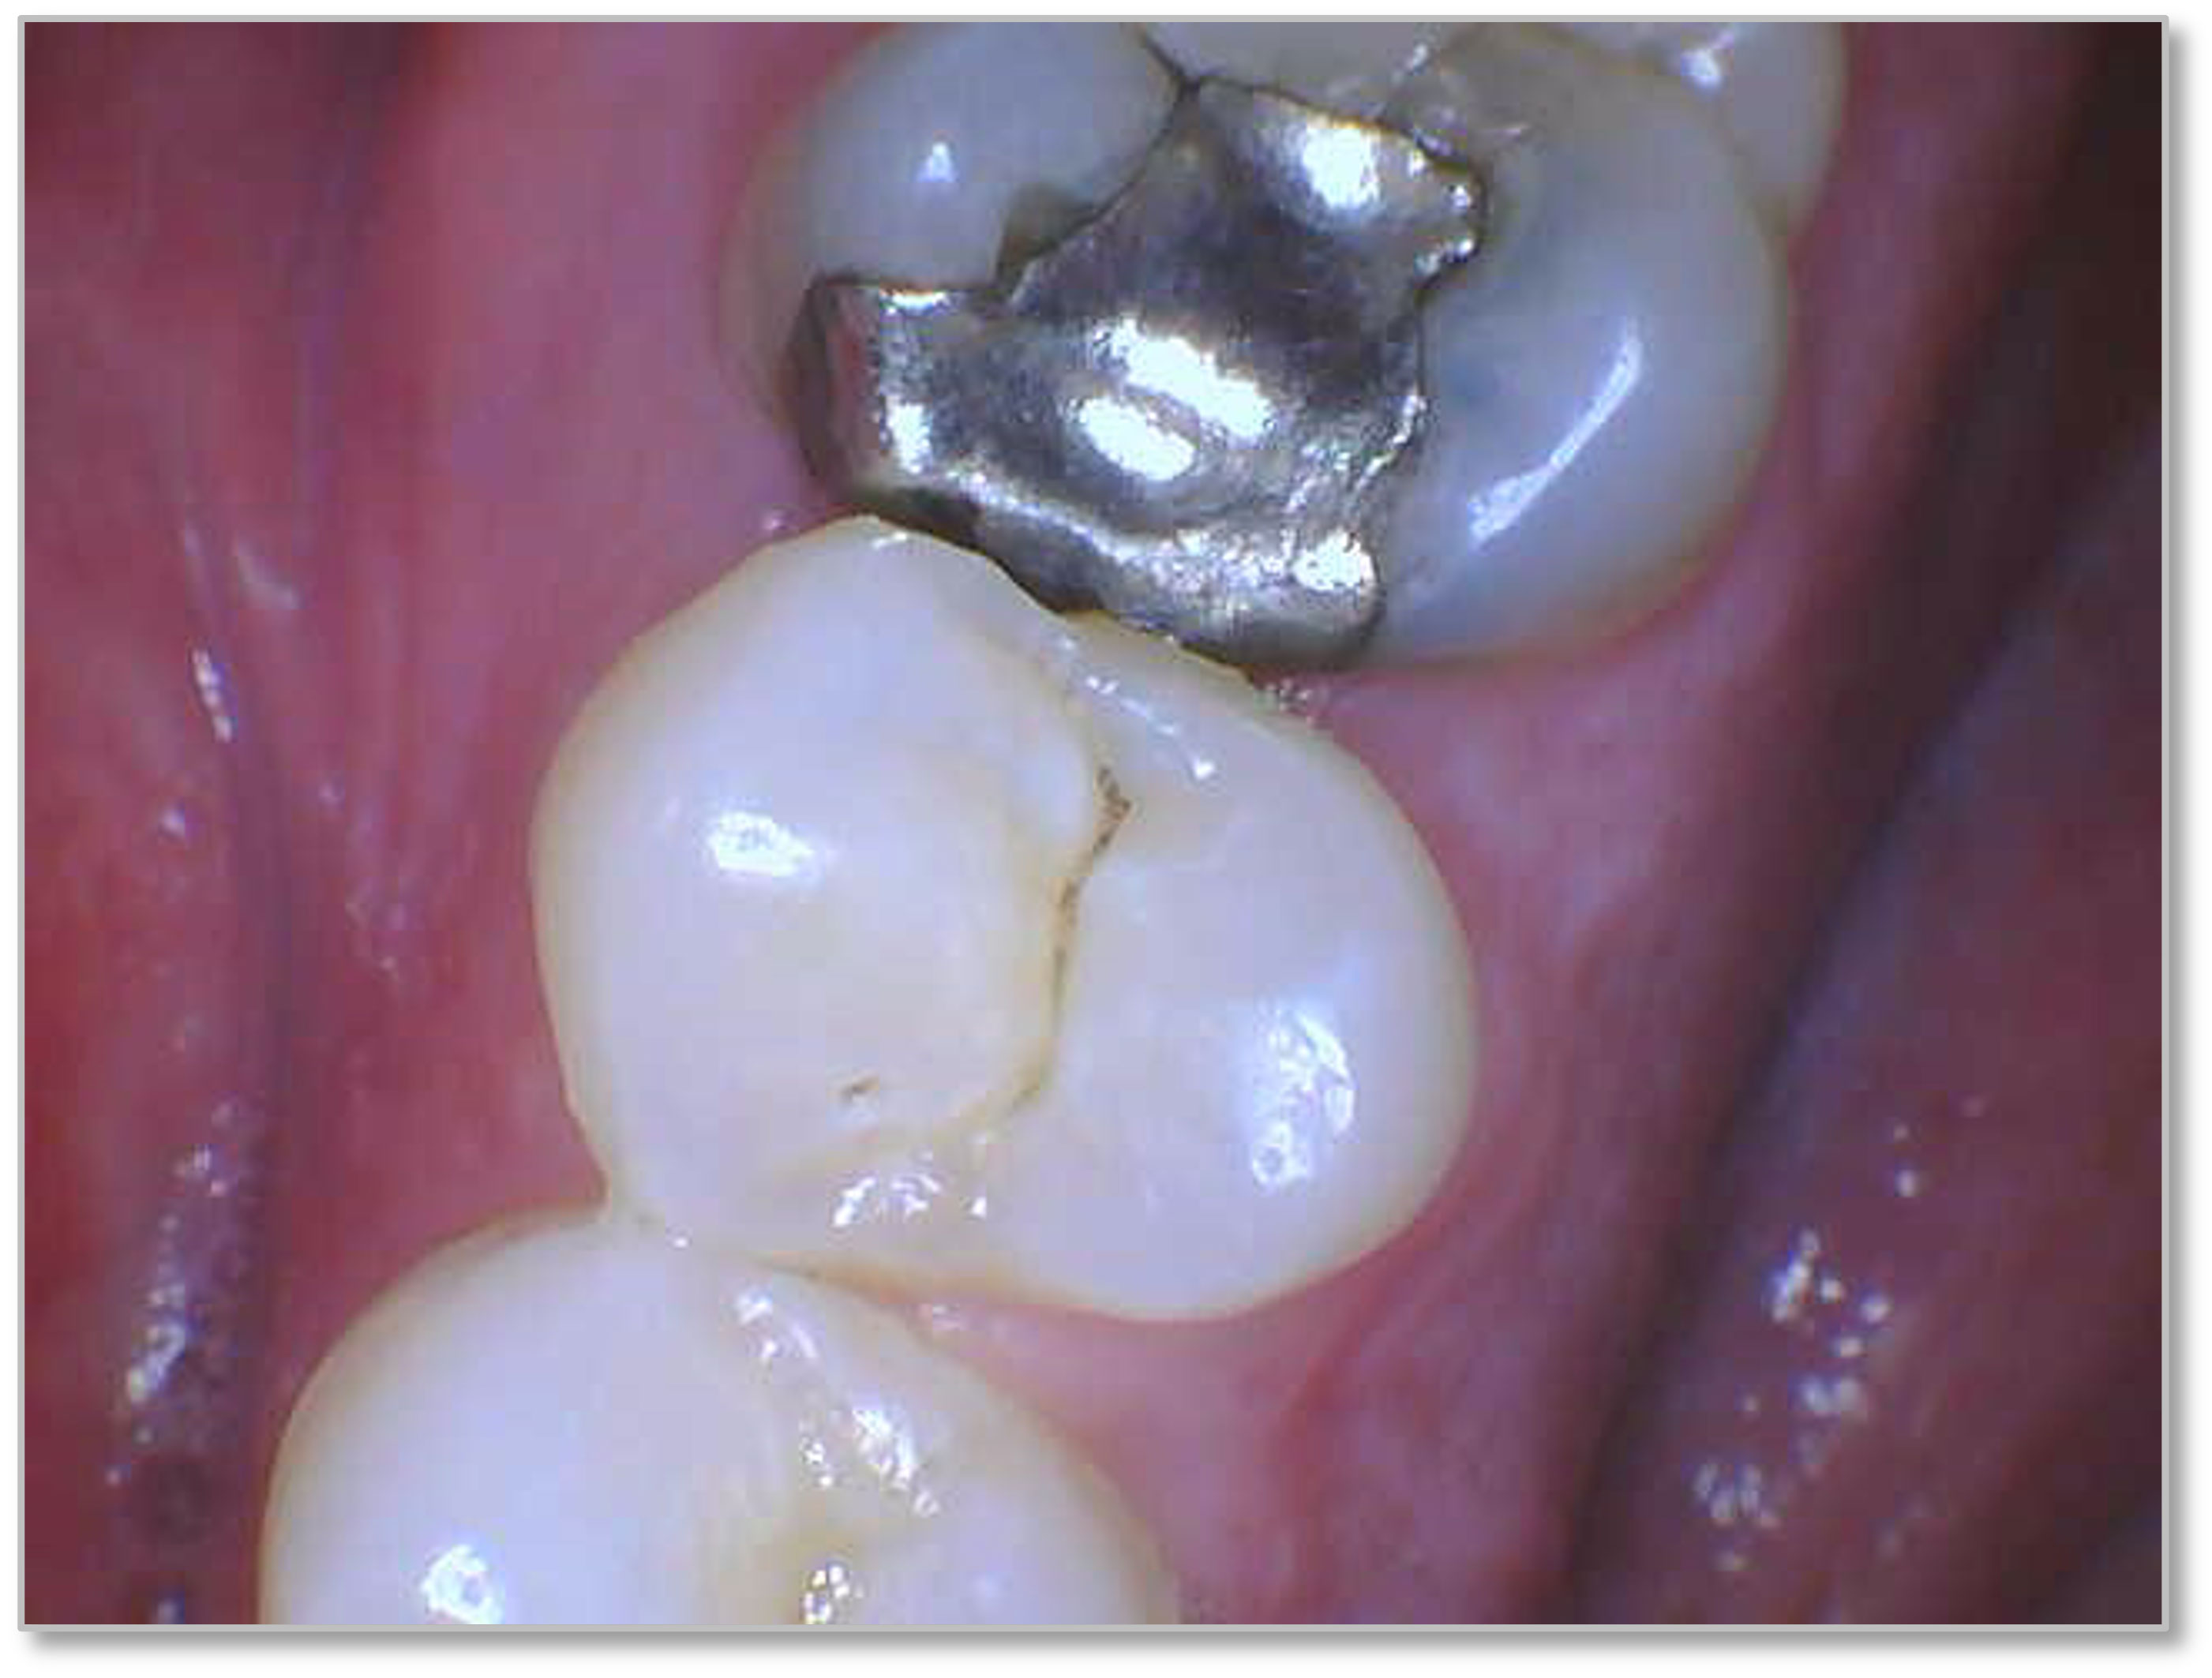

Figure 6a through Figure 6d show a procedure using a bulk fill packable as an interproximal Class 2, without using a bulk fill flow and not done with the snowplow technique to see how well the composite adapted to the margin. A light curable resin-modified calcium silicate liner (Bisco TheraCal LC) was used to perform an indirect pulp cap. A packable bulk fill composite was applied as a single increment layer to successfully restore the tooth. The material (Kerr SimpliShade Bulk Fill Packable) provided good adaptation to the tooth without gaps or polymerization stress lines and demonstrated great polishability and blendability. The patient reported no post operative sensitivity or discomfort in the 9 months after the restoration was performed. Sensitivity can be a concern if a composite is subjected to too much polymerization shrinkage.

Fig 6a. A procedure using a bulk fill packable as an interproximal Class 2, without using a bulk fill flow and not done with the

snowplow technique. A light curable resin-modified calcium silicate liner (Bisco TheraCal LC) was used to perform an indirect pulp cap. A

packable bulk fill composite was applied as a single increment layer. The material (Kerr SimpliShade Bulk Fill Packable) was used to provide

good adaptation to the tooth without gaps or polymerization stress lines and demonstrated great polishability and blendability.

Fig 6a. through 6d. A procedure using a bulk fill packable as an interproximal Class 2, without using a bulk fill flow and not done with the